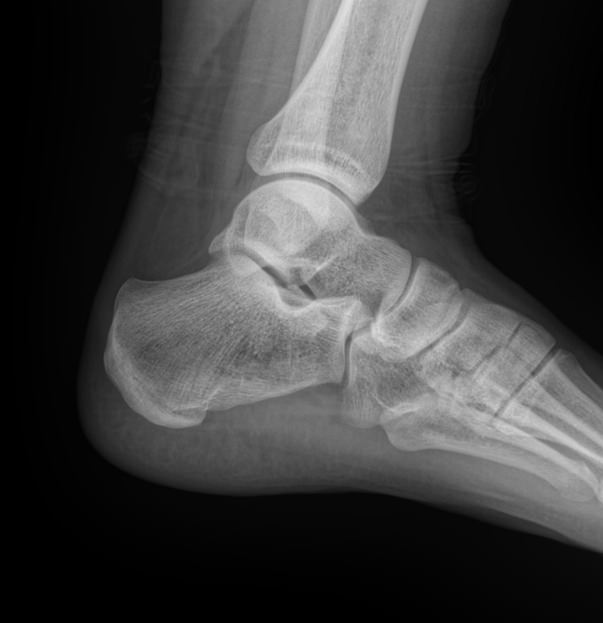

Назад Рентген пяточных костей в боковой проекции

Пяточная кость ― самая крупная среди костей стопы. Нагрузка, приходящаяся на нее, колоссальна. Отсюда и частая травматизация, связанная как со спортом, так и с бытовой и профессиональной деятельностью. Также все патологии, которые развиваются в костной ткани, могут появиться и в пяточной кости. Рентген ― наиболее часто назначаемый вид диагностики при поражении пятки.

На рентгенограмме будут отчетливо видны все структурные изменения, произошедшие с самой пяточной костью и тканями вокруг нее.

Что покажет рентген пяточных костей в боковой проекции

• Целостность кости: переломы, отломки, смещение;

• Состояние костной ткани: разрежение, склерозирование, некроз и другие изменения;

• Конгруэнтность суставных поверхностей и состояние щелей, попавших в область снимка: нормальные, измененные;

• Отечность и инородные тела в мягких тканях пятки;

• Новообразования: опухоли, остеофиты.

Стоит отметить, что остеофиты не являются причиной плантарного фасциита, а вырастают в ответ на хроническое раздражение мягких тканей и свидетельствуют о глубокой стадии заболевания.